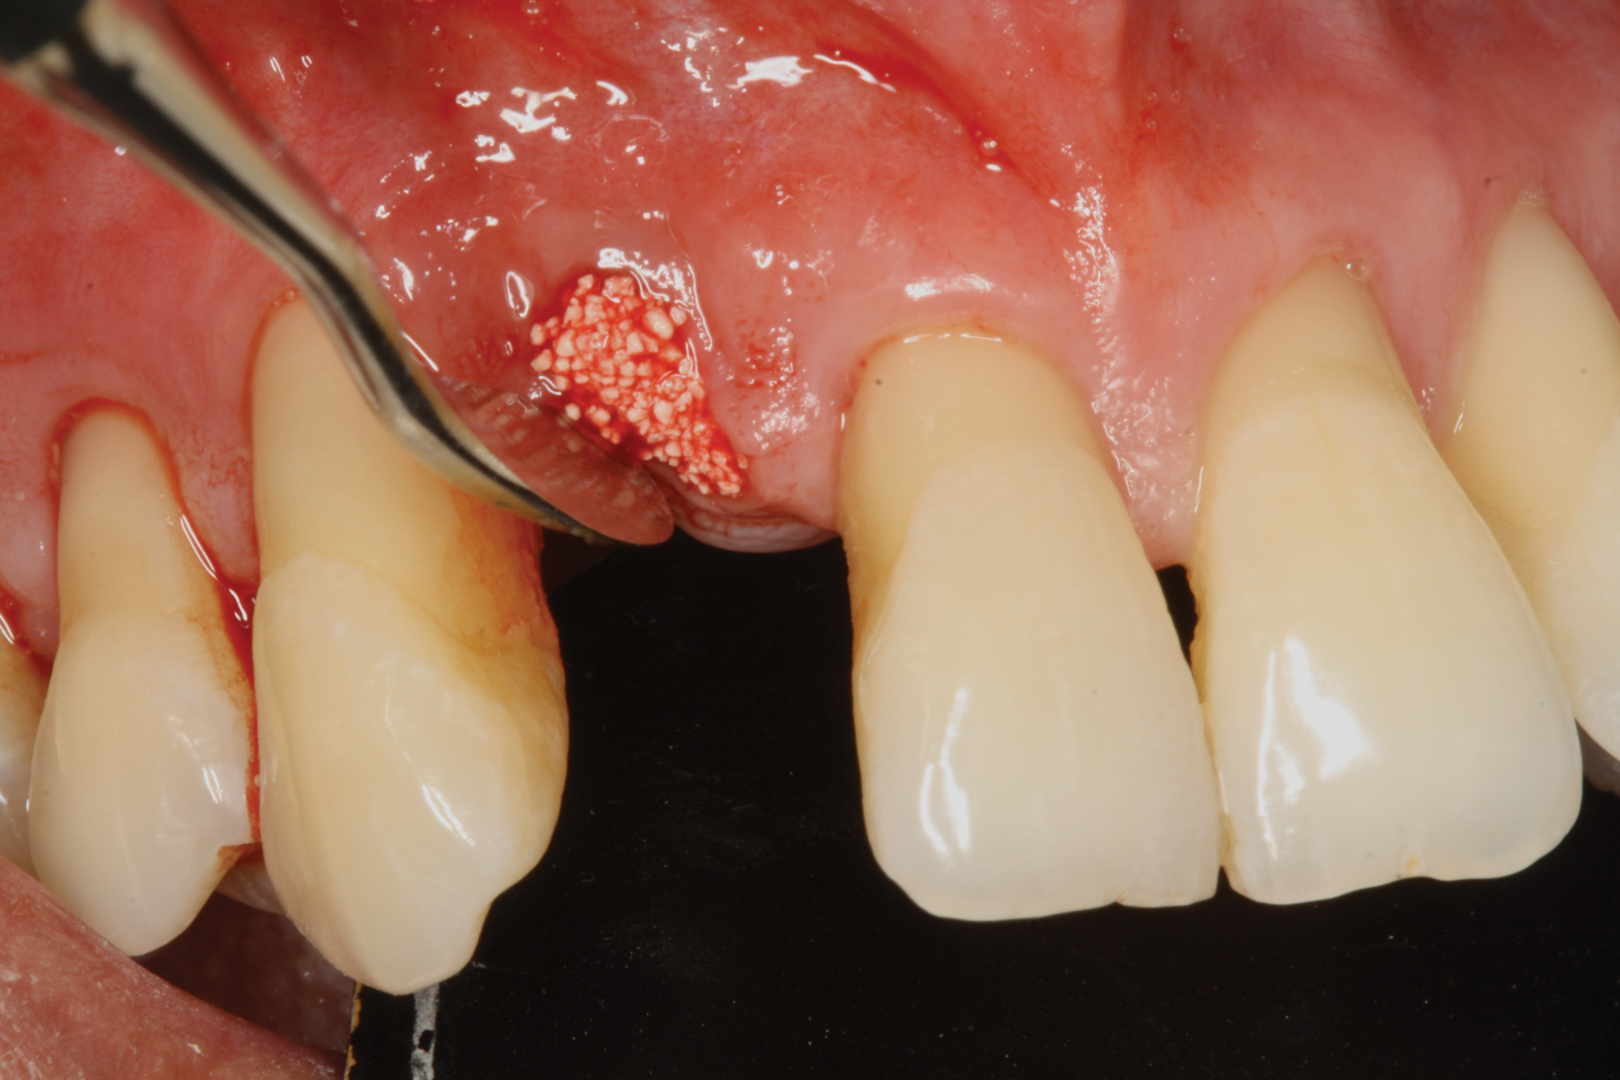

Fig 4. Sticky bone (i-PRF with bone graft) is another variant of i-PRF.

Figure 4

Fig 5. Sticky bone (i-PRF with bone graft) is another variant of i-PRF.

Figure 5

Bone grafts-When Mourão and coworkers first described liquid PRF in 2015, they demonstrated its polymerization, including with bone grafts.14 Bone graft materials still remain the most common component of any composite graft used in combination with i-PRF. Several forms of liquid PRFs, such as autologous fibrin glue (2700 RPM for 2 minutes), concentrated growth factor (accelerated for 30 seconds; centrifuged at 2700 RPM for 2 minutes, 2400 RPM for 4 minutes, 2700 RPM for 4 minutes, and 3000 RPM for 3 minutes; decelerated for 36 seconds to stop), and standard i-PRF (700 RPM for 3 minutes), have been mixed with various grafts to create composite grafts.28-32 In general, once the liquid form of PRF is obtained, it is mixed with particulate graft and left to polymerize. The resultant graft is a 3-dimensional polymerized matrix in which graft particles are encapsulated in a fibrin matrix. This has been referred to as sticky bone or sticky gel (Figure 4 and Figure 5).29,33